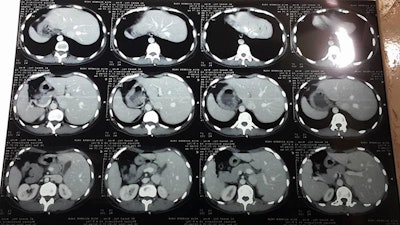

Between February 2015 and January 2018, 497 radiology exams were interpreted by TRG, including 374 CT scans (75%), 119 plain films (24%), and four ultrasound scans (1%). Most CT exams (97%) were performed without contrast, due to the shortage and prohibitive cost of contrast media.

The biggest challenge for TRG radiologists has been reading CT studies performed without contrast, particularly in trauma cases, according to Masrani and colleagues. Even the few contrast-enhanced CT scans are of low diagnostic value due to poor-quality scanners, improper timing of intravenous administration, and poor protocol and acquisition parameters.

"In some instances, submitted images were taken by cell phone camera capturing poorly projected radiographic films or printed CT images on viewing boxes," they wrote.